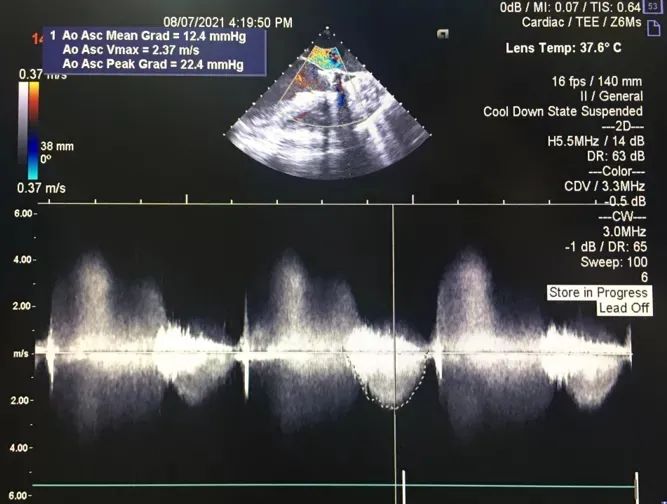

2.术前冠脉造影,提示左冠中段存在狭窄,TEE 见大量反流影;

在释放末段,通过牵拉冠脉支架完成 TAVR-烟囱支架置入术。术后即时造影示少量瓣周漏,测量跨瓣压差示平均压差 12mmHg。经讨论,考虑到冠脉支架与瓣膜自膨胀支架可能存在接触间隙,遂行球囊后扩。后扩后跨瓣压差进一步降低,得到理想的手术效果。